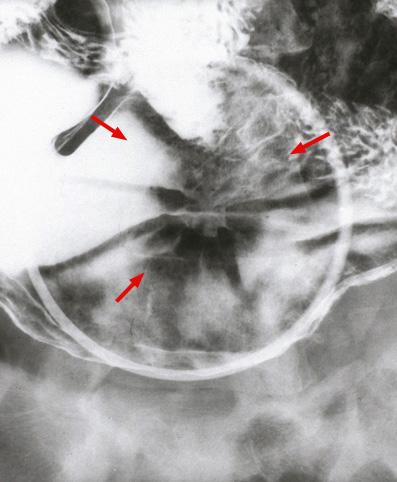

clasificación del pacienteTumor Epitelial Maligno/Cáncer a células en Sello de Anillo

parte(separada por órganos)estómago(región)/cuerpo

método de exámenRayos X

clasificación ectoscópica de tumoresTipo 0(tipo superficial)/Tipo IIc(IIc+III)

diámetro mayor del tumor25 - 29

grado de penetraciónsm